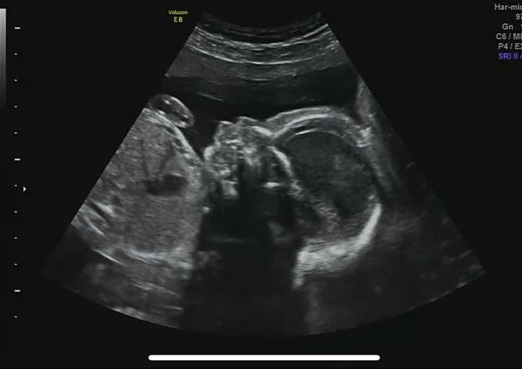

둘째일기/15주-23주/기형아검사, 니프티검사, 정밀초음파

그동안 임신 기록을 산부인과 방문 주기에 맞춰서 한달에 한번 정도는 올렸었는데, 지난 달은 글을 올리지 ...